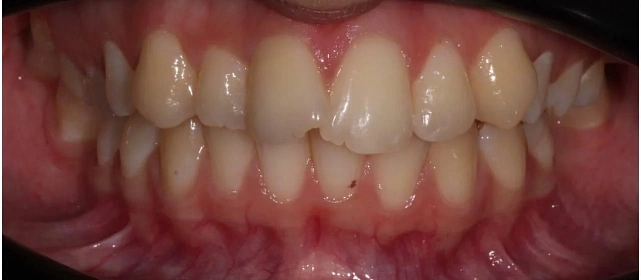

Проблема: В клинику обратилась пациентка — беспокоили неровные зубы и неправильное смыкание. Зубные ряды сходились некорректно, зубы стояли со смещением, что влияло и на внешний вид, и на распределение нагрузки при жевании.

Решение: Поставили элайнеры 3D Smile на обе челюсти. Лечение заняло 4 года и потребовало нескольких последовательных этапов коррекции. Капы менялись каждые 1–2 недели, на контрольных визитах отслеживали прогресс и выдавали новые наборы. Зубы встали в правильное положение, смыкание нормализовалось. Зафиксировали ретейнеры на обе челюсти, изготовили ретенционные капы. Пациентка прошла онлайн-консультацию с ортопедом для оценки дальнейших шагов.

Результат

Зубы выровнены, смыкание нормализовано. Установлены несъёмные ретейнеры на обе челюсти, изготовлены ретенционные капы. Пациентка предварительно проконсультирована ортопедом онлайн.